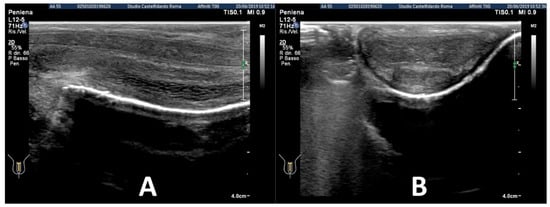

| 2 | 52 years | Dupuytren’s disease, Ledderhose disease, congenital dorsal penile curvature (5 degrees). | Middle third + distal third | (A) First plaque: 13.4 × 9.15 × 2.83 mm volume = 182 mm3. Second plaque: 14.8 × 8.43 × 3.87 mm. Total volume = 252 mm3 (B) No plaque detected | (A) 20-degree dorsal penile curvature + 20-degree left penile curvature (B) 5-degree dorsal penile curvature. Previous condition = congenital dorsal penile curvature (5 degrees) | VAS score = 0 | 26 > 27 | 51 months | Orally: propolis 600 mg + bilberry 160 mg + silymarin 400 mg + ginkgo biloba 250 mg + L-carnitine 1000 mg + coenzyme Q10 100 mg + Boswellia 200 mg + vitamin E 30 mg/daily for 51 months + topically: diclofenac gel 4%/2× daily for 51 months + periplaque penile injections: pentoxifylline 100 mg (30 G needle) every 2 weeks for 6 months, and then 1 penile injection every month for 12 months, and 1 penile injection every 2 months for 24 months (42 total injections) |